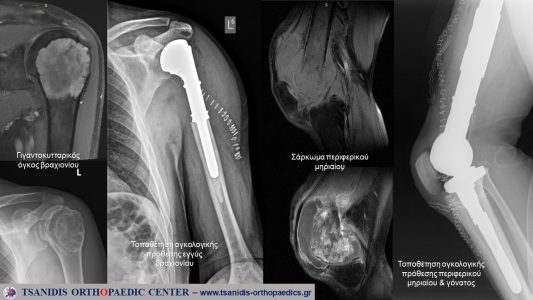

Οι όγκοι αυτοί εμφανίζονται στα άκρα, χέρια και στα πόδια, στο κοιλιακό τοίχωμα, στη ράχη και στη λεκάνη. Οι όγκοι αυτοί μπορεί να είναι καλοήθεις ή κακοήθεις (σαρκώματα). Πιο συχνοί τέτοιοι όγκοι είναι το λίπωμα, το λιποσάρκωμα, το οστεοσάρκωμα, ο γιγαντοκυτταρικός όγκος, η ανευρυσματική κύστη, το οστεοειδές οστέωμα, το ίνωμα, το σάρκωμα Ewing, το εγχόνδρωμα, το χονδροσάρκωμα, το συνοβιακό σάρκωμα, το ίνωμα, το χόρδωμα, η εξόστωση, το οστεοβλάστωμα και αρκετοί άλλοι.

Συνήθως η θεραπεία είναι η χειρουργική. Η χημειοθεραπεία, η ανοσοθεραπεία και η ακτινοθεραπεία, συνεισφέρουν αποφασιστικά στην βελτίωση της θεραπείας και της επιβίωσης. Κάθε όγκος έχει συγκεκριμένο πρωτόκολλο θεραπείας το οποίο ακολουθείται από τους εξειδικευμένους γιατρούς και διαφέρει από όγκο σε όγκο αλλά κι ανάλογα με τον τύπο του ίδιου όγκου. Μικρές λεπτομέρειες, ακόμα από την διάγνωση και στον τρόπο βιοψίας μπορεί να είναι αποφασιστικές για τη ζωή του ασθενούς. Όσον αφορά στη χειρουργική θεραπεία, υπάρχουν πλέον διαθέσιμες προθέσεις (ακόμα κι εκπτυσσόμενες παιδο-ογκολογικές) ή μοσχεύματα για να αντικαταστήσουν τα τμήματα των οστών που πρέπει να αφαιρεθούν. Η χειρουργική διάσωσης άκρων – είναι η χειρουργική που αποτρέπει τον ακρωτηριασμό – με τη νέα τεχνολογία, πλοήγησης και της αξιολόγησης ψηφιακά του όγκου, προσφέρει εξαιρετικά αποτελέσματα, σύμφωνα με τα διεθνή κριτήρια αξιολόγησης και αφορούν όχι μόνο στην επιβίωση του ασθενούς αλλά και στη λειτουργικότητα του χειρουργημένου άκρου.